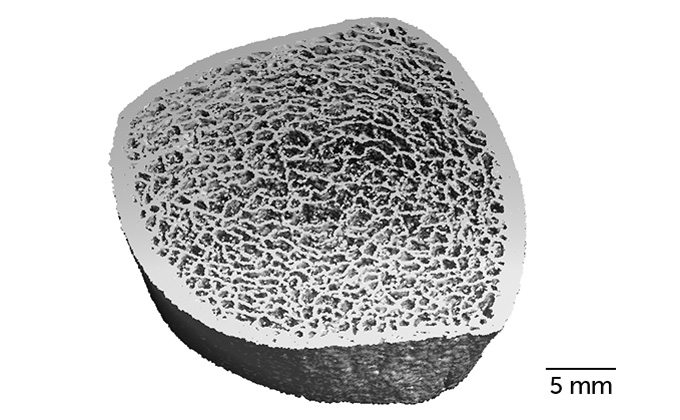

Gabel and her colleagues tracked 17 astronauts, 14 men and three women with the average age of 47, who spent from four to seven months in space. The team used high-resolution peripheral quantitative computed tomography, or HR-pQCT, which can measure 3-D bone microarchitecture on scales of 61 microns, finer than the thickness of human hair, to image the bone structure of the tibia in the lower leg and the radius in the lower arm. The team took these images at four points in time — before spaceflight, when the astronauts returned from space, and then six months and one year later — and used them to calculate bone strength and density.

Astronauts in space for less than six months were able to regain their preflight bone strength after a year back in Earth’s gravity. But those in space longer had permanent bone loss in their shinbones, or tibias, equivalent to a decade of aging. Their lower-arm bones, or radii, showed almost no loss, likely because these aren’t weight-bearing bones, says Gabel.

Increasing weight lifting exercises in space could help alleviate bone loss, says Steven Boyd, also a Calgary exercise scientist. “A whole bunch of struts and beams all held together give your bone its overall strength,” says Boyd. “Those struts or beams are what we lose in spaceflight.” Once these microscopic tissues called trabeculae are gone, you can’t rebuild them, but you can strengthen the remaining ones, he says. The researchers found the remaining bone thickened upon return to Earth’s gravity.